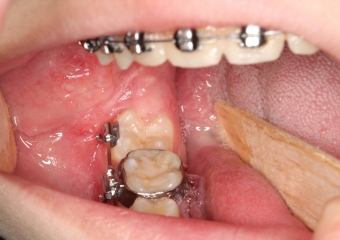

Extração dos 4 terceiros molares  - Instalação de placas de ancoragem - Clínica Cliniface

Extração dos 4 terceiros molares - Instalação de placas de ancoragem